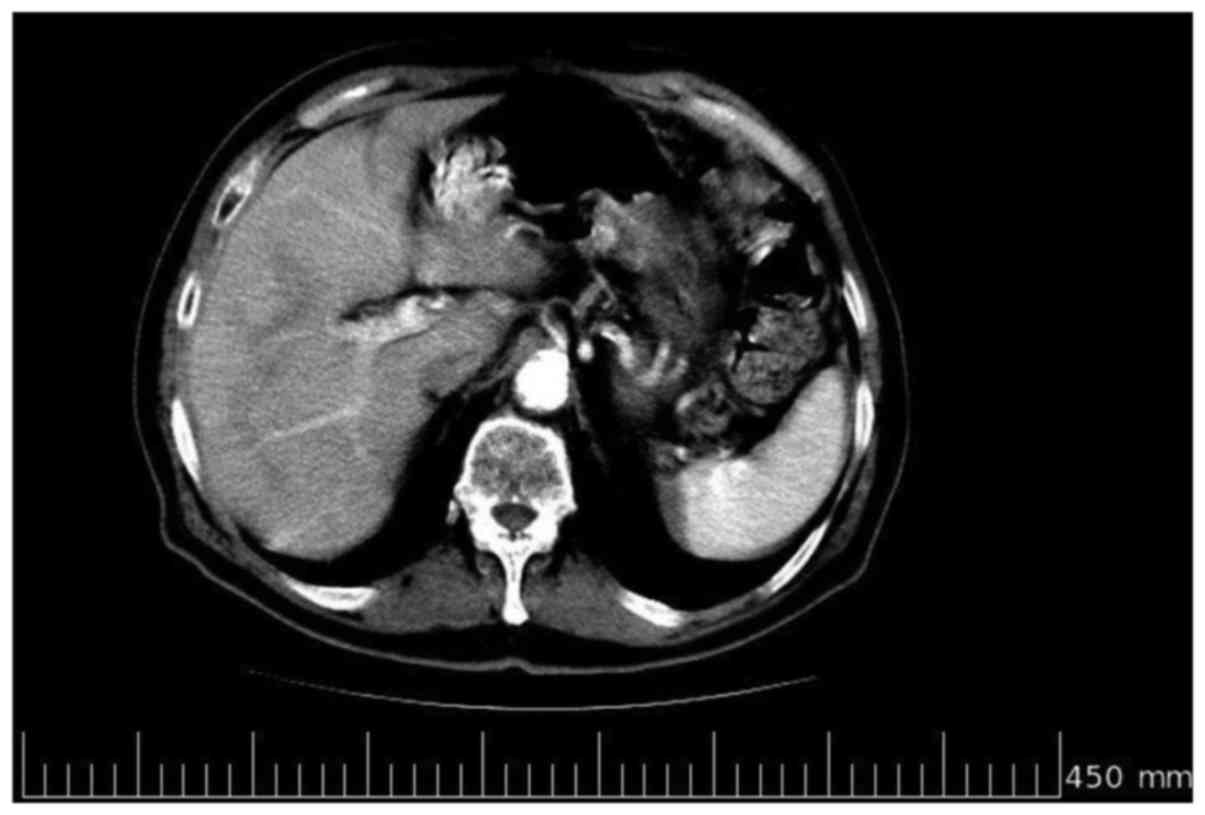

resulted in the continuation of the therapy. In June 2009, after 6

further cycles of the chemotherapy, a further total-body

contrast-enhanced CT scan was performed, which revealed evidence of

a complete response, with no evidence of liver metastases (Fig. 3). Due to the length of treatment and

the evidence of a complete response, chemotherapy was discontinued,

whilst clinical-instrument examination was continued with

contrast-enhanced CT every 6 months, abdominal ultrasound

examination and annual colonoscopy and laboratory haematological

examination and tumor marker level assessment (CEA, CA19.9 and

CA125) every 3 months. In July 2010, a contrast-enhanced CT scan

confirmed the complete response (Fig.

4). However, the patient succumbed to a diabetes-related

complication in October 2010 following 29 months of overall